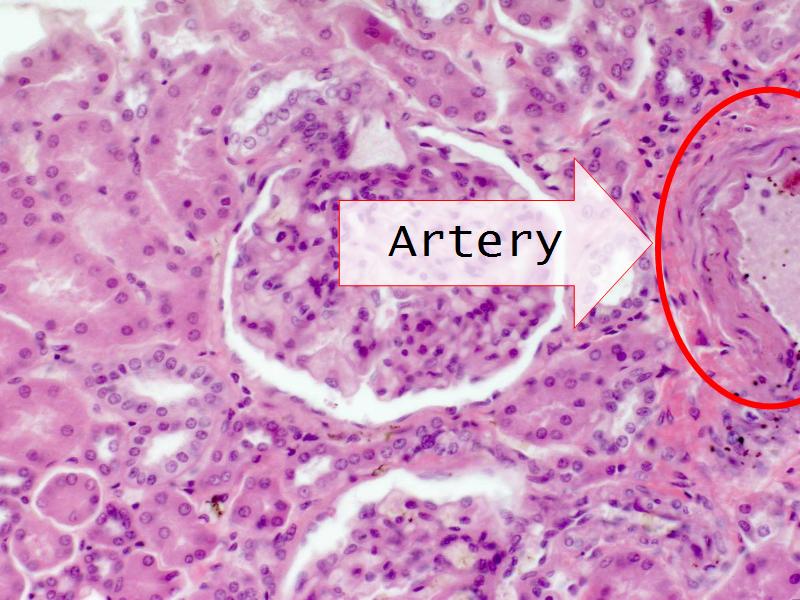

- The renal corpuscle

Nephron